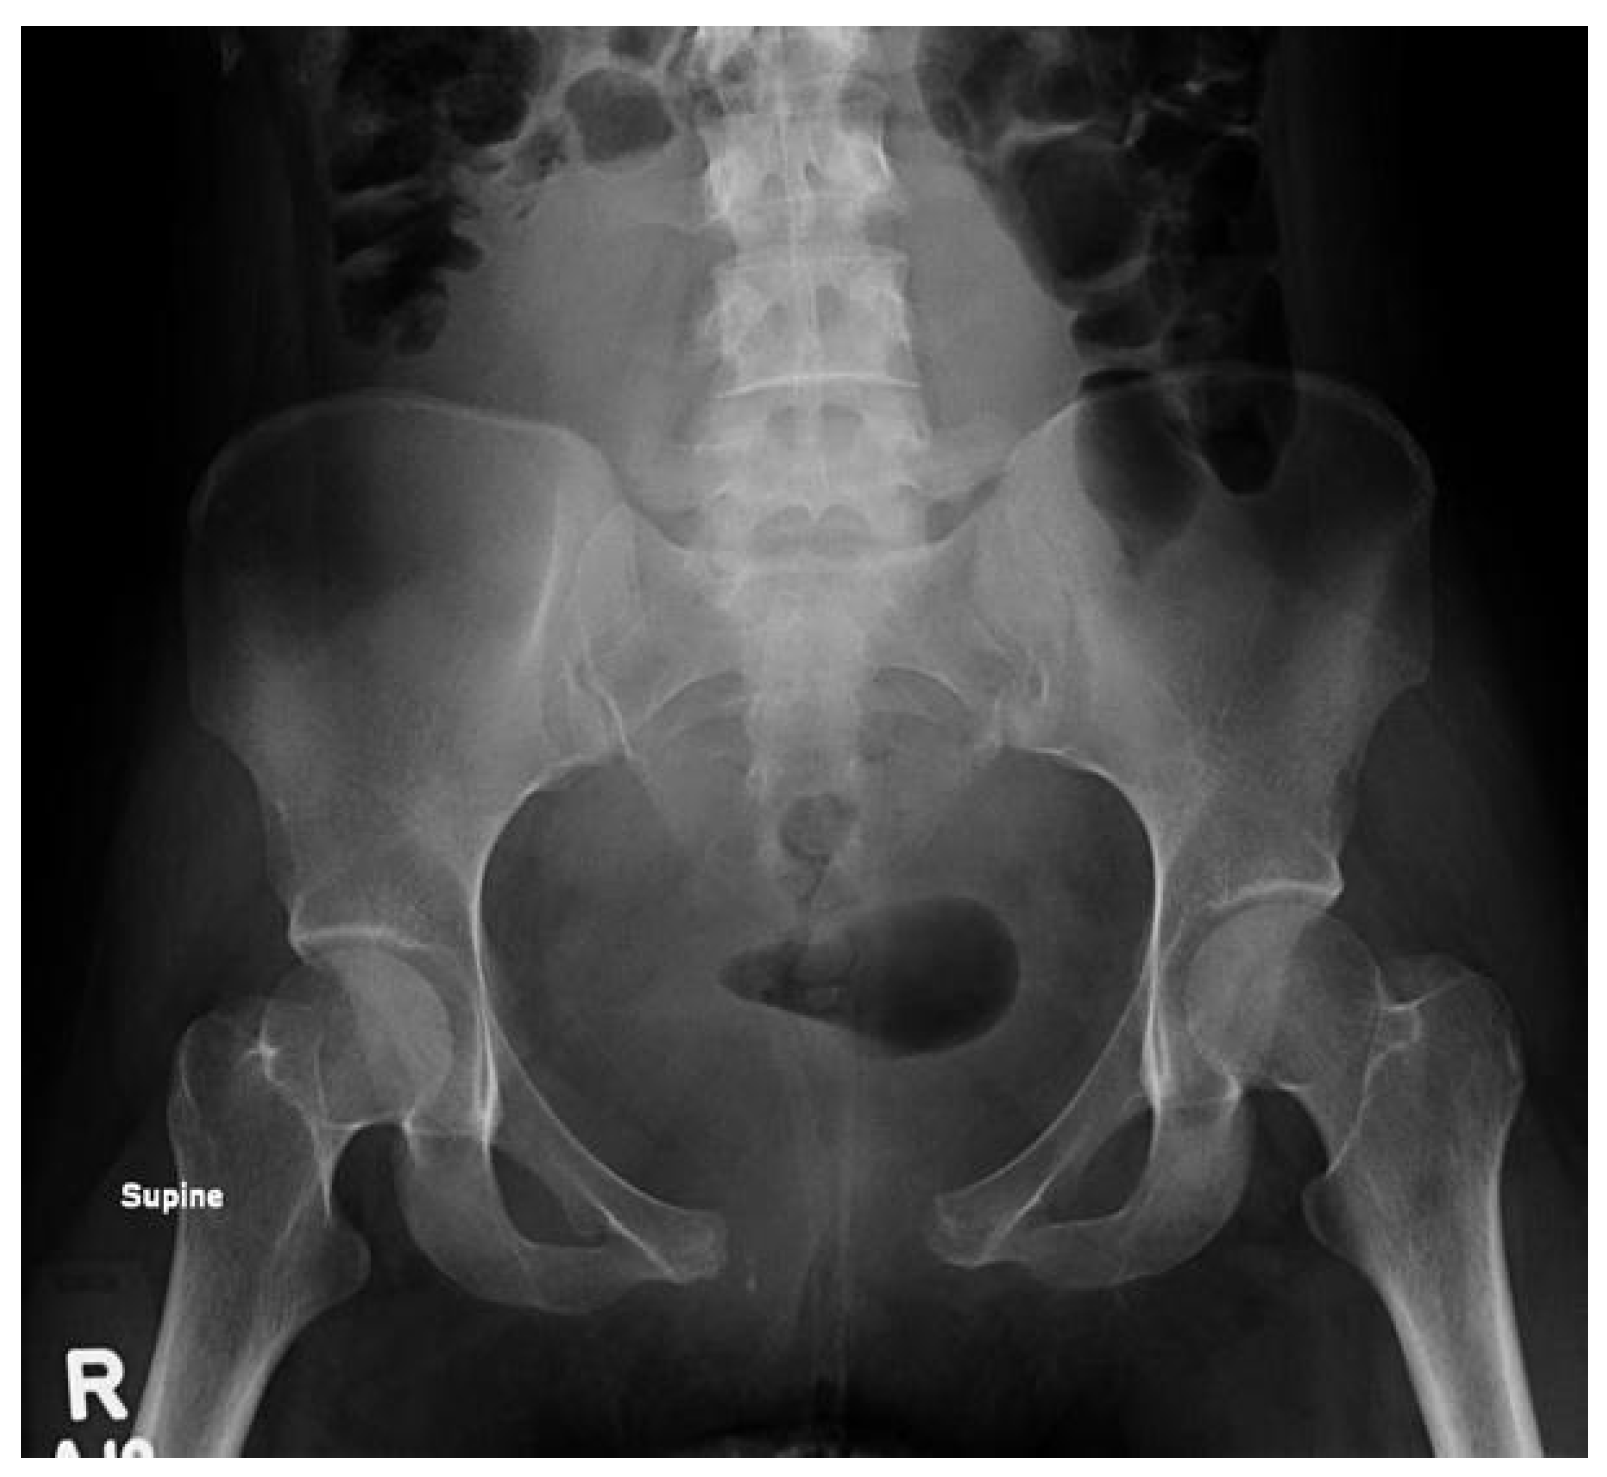

Radiographs were obtained, revealing a 5.0 cm separation of the pubic symphysis and anterior widening of the sacroiliac joint (Figure 1). A pelvic binder was placed to provisionally stabilize the pelvis, and the patient was immediately transferred to a higher level of care for evaluation and management.

Figure 1. Initial AP pelvis radiograph on presentation demonstrating a 5.0 cm separation of the pubic symphysis and anterior widening of the sacroiliac joint.